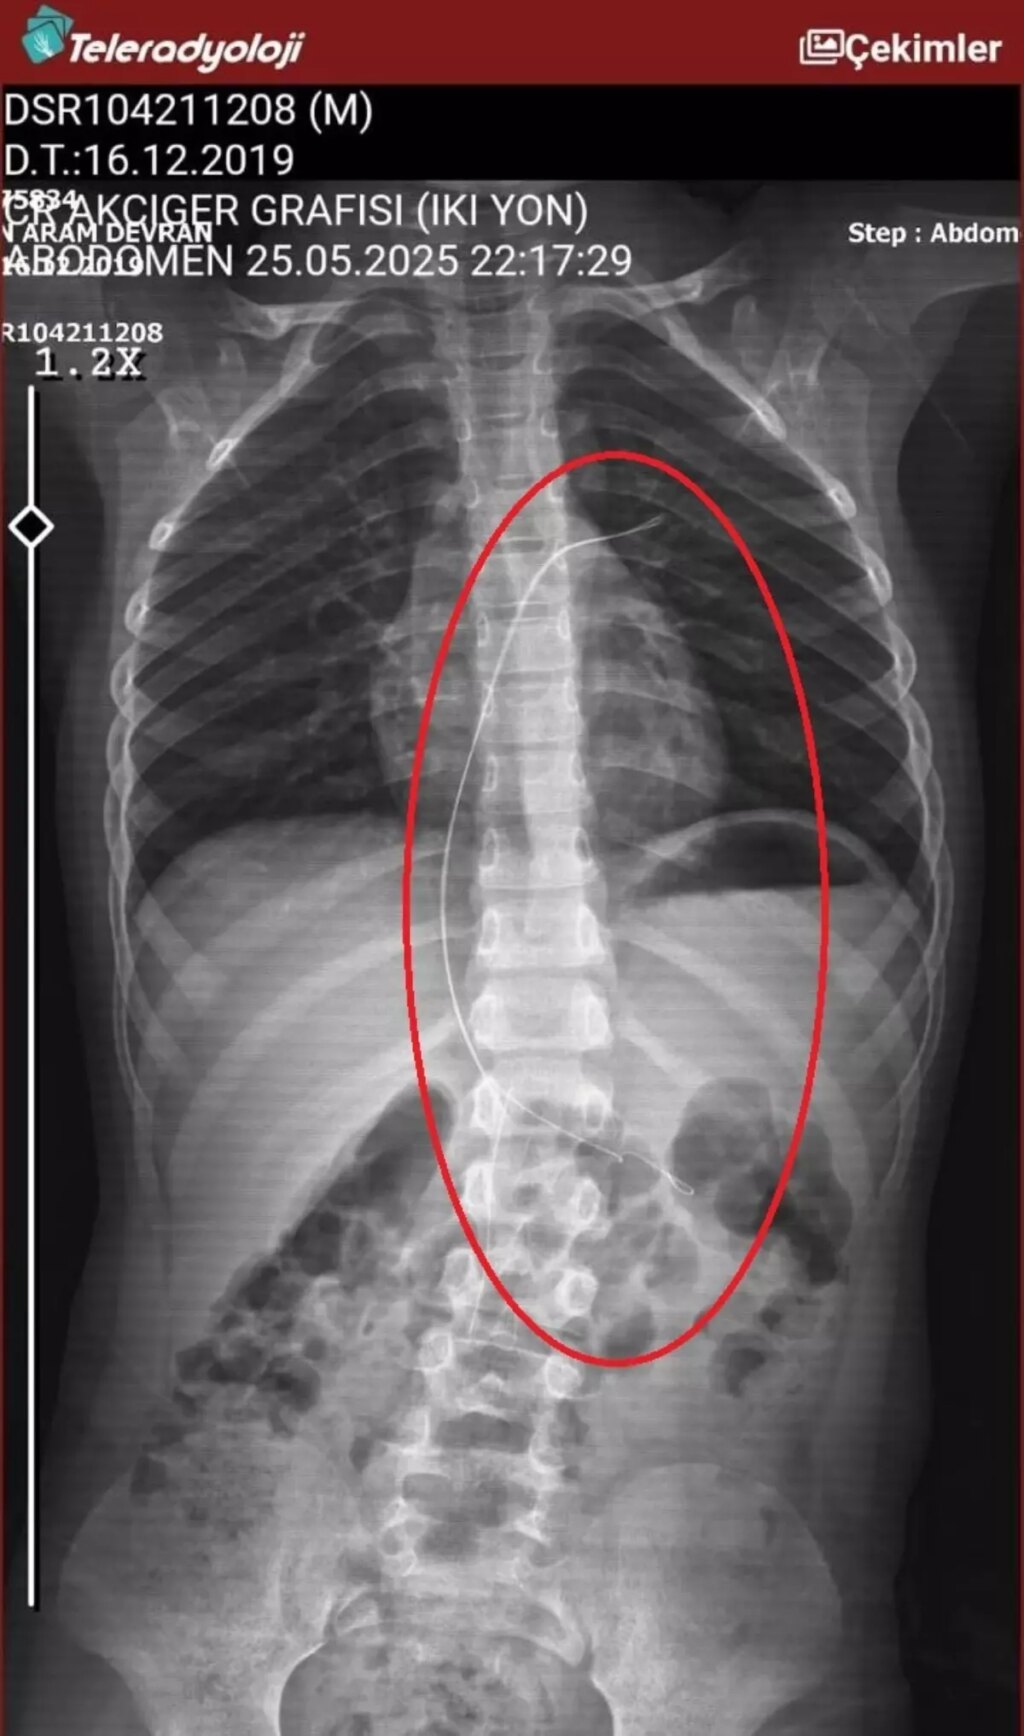

ŞIRNAK'ta piknikte salatalık kesimi yuttuktan sonra öksürük ve kusma şikayetleriyle hastaneye götürülen Aram Devran Ötün'ün (6), 3 yıl evvel Stevens- Johnson sendromu nedeniyle tedavi gördüğü sırada damar yoluna takılan 18 santimetrelik kateterin bedeninde unutulduğu ortaya çıktı.

ŞIRNAK’ta piknikte salatalık kesimi yuttuktan sonra öksürük ve kusma şikayetleriyle hastaneye götürülen Aram Devran Ötün’ün (6), 3 yıl evvel Stevens- Johnson sendromu nedeniyle tedavi gördüğü sırada damar yoluna takılan 18 santimetrelik kateterin bedeninde unutulduğu ortaya çıktı. Öğüt, 5,5 saat süren riskli bir ameliyatla kateterden kurtuldu.

Şırnak’ta yaşayan Semra (37) ve Mehmet Ötün (40) çiftinin oğulları Aram Devran Ötün, mayıs ayında piknikteyken salatalık kesimi yuttuktan sonra öksürük ve kusma şikayetleri görülünce Şırnak Devlet Hastanesi’ne götürüldü. Burada çekilen röntgen ve MR’da Aram’ın bedeninde kateter unutulduğu görüldü. Diyarbakır’daki Gazi Yaşargil Eğitim ve Araştırma Hastanesi Bayan Doğum ve Çocuk Ek Binası’na sevk edilen Aram, 5,5 saat süren riskli bir ameliyata alınarak 18 santimetre uzunluğundaki kateter çıkarıldı. Ameliyat sonrası yapılan incelemelerde kateterin kalp kapakçığına ve ciğerlerine ziyan verdiği belirlendi.

Oğlunun piknikte salatalık modülü yuttuktan sonra daima öksürmeye ve kusmaya başladığını söyleyen Semra Ötün, “Çocuğum 3 yıl evvel Steven Johnson sendromu hastalığına yakalandı. Milyonda bir görülen antibiyotikten kaynaklı bir hastalık. Hekimler o denli söyledi. Bizi hemen Diyarbakır Dicle Üniversitesi Çocuk Hastanesi kısmına sevk ettiler. 1 ay ağır bakım sürecimiz oldu. 28 gün ağır bakımda, 3 günde serviste kaldı. Damar yolundan, kasıktan serum taktılar. Kateter denilen tel çocuğun bedeninde bırakılıyor. Biz taburcu olduğumuzda fark edilmiyor. 3 yılın sonunda biz bunu fark ettik. Pikniğe gittik. Oğlum salatalık kesimi yuttu ve salatalık modülünden sonra akşama kadar öksürdü. Hiçbir halde durmadı. Kusuyordu. Ben şüphelenmeye başladım. Çocuğum olağan değildi. Sonra eşime danıştım. Akşam 21.00 civarında acile götürdük. Röntgeni ve MR’ı çekildi. Tuhaf bir şey olduğunu anladık. Doktor röntgeni gösterdi. Tel kalmıştı. Çok makus bir biçimde. Acil tabibi sinema çektikten sonra bize bir tel modülünü gösterdi. Bizi bekletmeden Diyarbakır’a sevkimizi verdiler. Diyarbakır Gazi Yaşargil Eğitim ve Araştırma Hastanesi Bayan Doğum ve Çocuk Ek Binası’na gittik. Çocuğun kasıklarından anjiyo yolu ile teli çıkaracaklarını fakat riskli bir ameliyat olduğunu söylediler. O süreçte çocuk hakikaten daima yoruluyordu. İkide bir oturuyordu. ‘Anne çok yoruldum, karnım ağrıyor’ diyordu. Ben ağrı kesiciler ile geçiştirmeye çalışıyordum. Bu telin 3 yıl boyunca çocuğumda kaldığını öğrendim. Ailece yıkıldık” diye konuştu.

“Çocuğum yaklaşık 5,5 saat ameliyatta kaldı. Ameliyata giren doktor kötü bir şekilde çıkıyordu. Çok sıkıntı bir yerde olduğunu ve yorulduklarını söylüyordu. Gereç atıyoruz, gereç geliyor tel hiçbir gelmiyor, dedi. Sonra en son bir doktor çıktı, ‘İki seçeneğimiz var. ya açık kalp ameliyatı ya da çocuk ömür uzunluğu o tele maruz kalacak’ dediler. Her iki seçenekte benim için çok acıydı. Sonra profesör girdi ameliyatına başardılar. Çıkardılar. Şu anda kalp kapakçığında sorun varmış. Çocuğum bundan ötürü tedavi oluyor. Çok acılı günler geçirdik. Çok güç günler geçirdik. Bizim canımız yandı kimsenin canı yanmasın. Hekimler söylediğinde inanamadım. Şok oldum. Zira çocuğum 3 sene boyunca takipli hasta olduğumuz için daima Diyarbakır’a, Ankara’ya daima gidip geliyoruz. İnanamadım ben. Kendi gözlerimle görmeyene kadar inanmadım. Çok makûs olduk.”